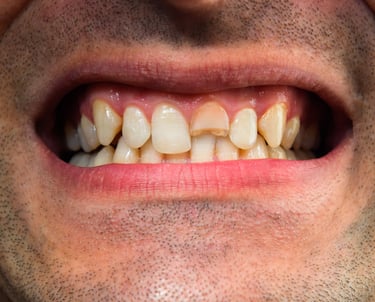

Se revisa si hay fracturas en la parte visible del diente. Las fracturas de la corona pueden ser causadas por trauma o caries extensas y pueden afectar el tratamiento endodóntico.

Evaluación de fracturas de la corona